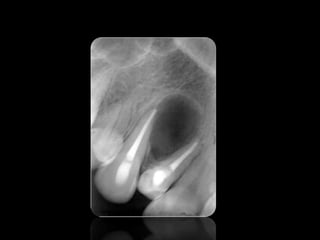

ABSCESO PERIAPICAL